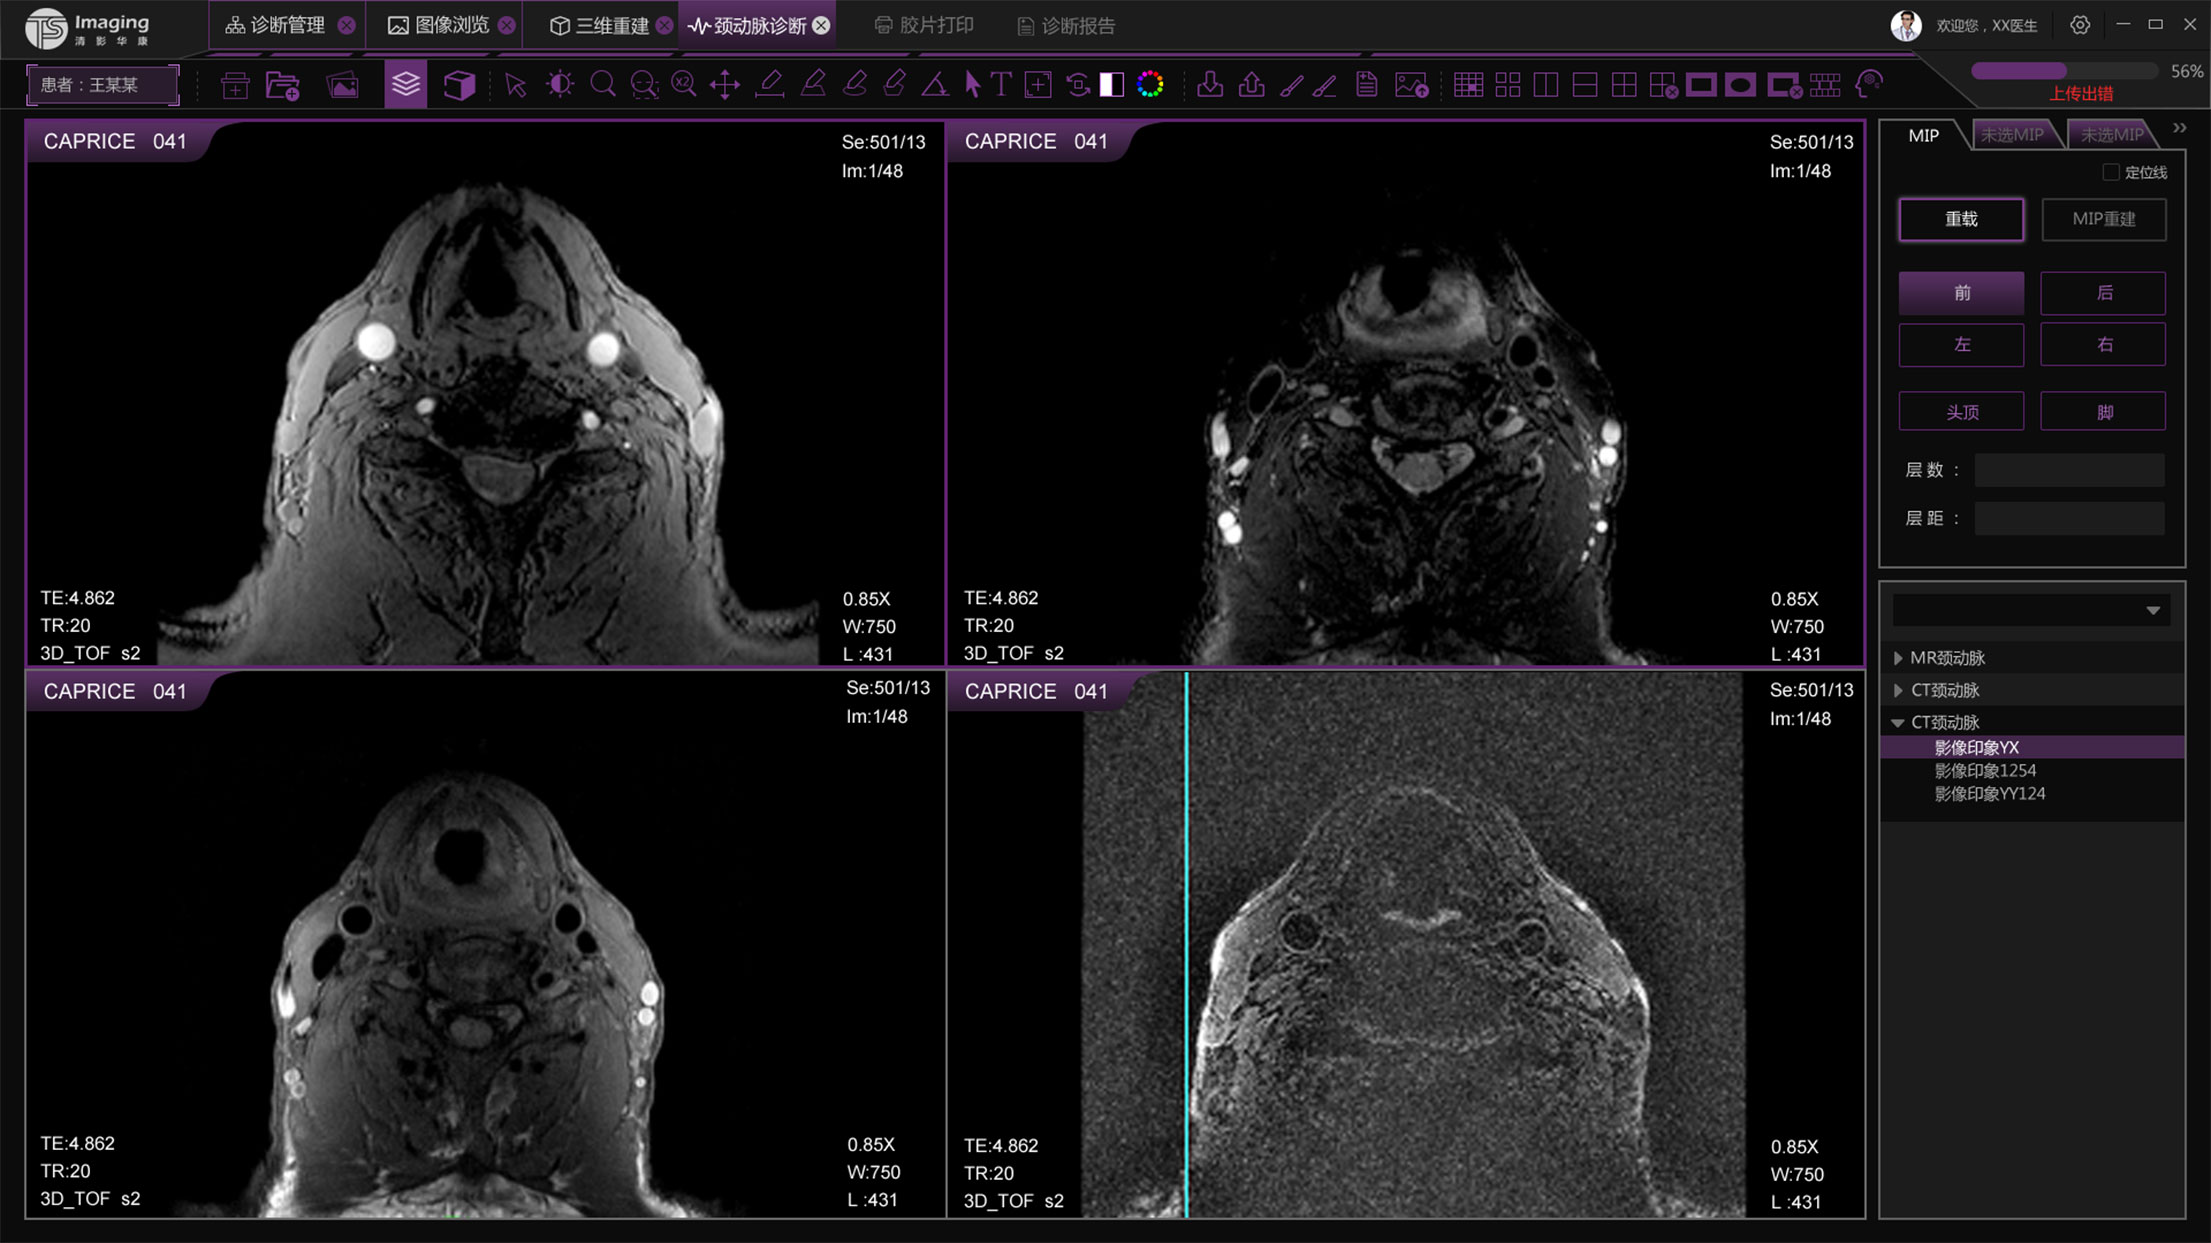

頸動脈診斷頁面

頸動脈診斷頁面整體布局和三維重建比較相似,最大的區別是右側的操作區域,血管分析都為按鍵操作,通過間隔的大小分成三部分。單層切片除了按鍵還有下拉菜單的操作。